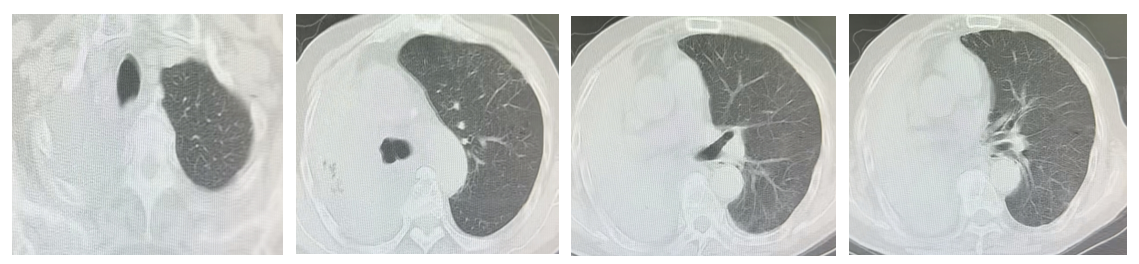

此前,一颗恶性肿瘤在唐爷爷右主支气管内疯狂生长,将这条生命通道彻底堵死。有慢阻肺病史的他,轻微活动便呼吸困难,每一次吸气都如濒死挣扎。在家人的陪同下,唐爷爷来哈医大一院群力院区呼吸内科于世寰主任处就诊。经肺部CT显示,他的右肺门及气管内占位、双肺炎症伴右肺不张,情况危急。

“老人高龄,手术风险倍增,但放任不管就是眼睁睁看着生命流逝。”呼吸内科于世寰主任牵头,联合麻醉科等部门反复评估,并与家属充分沟通后,11月14日,在麻醉科文质斌医生配合下,于世寰主任和张春玲副主任医师、吴昊岚主管护师一起率先为老人实施支气管镜下削瘤治疗。术后老人呼吸一度好转,但镜下削瘤治疗新生物进展较快,三天后,唐爷爷病情突发反复,右肺完全不张,呼吸功能再次衰竭。

图1 第一次支气管镜介入治疗三天后复查肺CT(右肺完全不张)